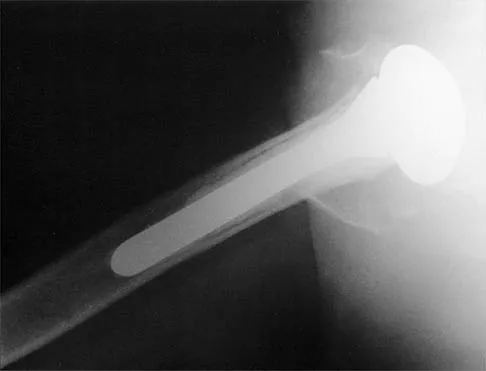

A 28-year-old man sustained a shoulder dislocation 2 years ago. It remained dislocated for 3 weeks and required an open reduction. He now reports constant pain and has only 60 degrees of forward elevation and 10 degrees of external rotation. He desires to return to some sporting activities. An AP radiograph and intraoperative photograph (a view of the humeral head through a deltopectoral approach) are shown in Figures 31a and 31b. What is the best treatment option to decrease pain and improve function?

The radiograph and intraoperative photograph show osteonecrosis with near complete head loss/collapse. A stemmed implant is more appropriate in this patient because there is very little bone to support a resurfacing implant. In a younger patient, a glenoid implant should be delayed as long as possible because of the eventual need for revision secondary to glenoid loosening and wear, especially in a young active male. The hemiarthroplasty may be converted to a total shoulder arthroplasty in the future. Levy O, Copeland SA: Cementless surface replacement arthroplasty of the shoulder: 5- to 10-year results with the Copeland mark-2 prosthesis. J Bone Joint Surg Br 2001;83:213-221.